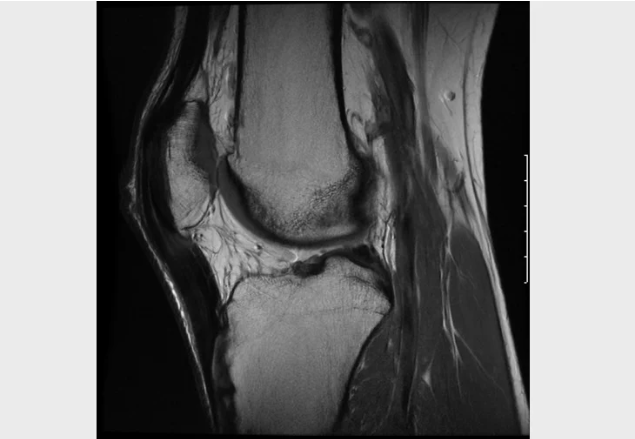

With tendinopathy in the mid portion of the patella tendon.

Tendinitis located at the distal tip of the patella.

Localised to the anterior knee, at the mid portion of the patella tendon

Pain on palpation of patella tendon

Image from OpenI – Licensed by CC